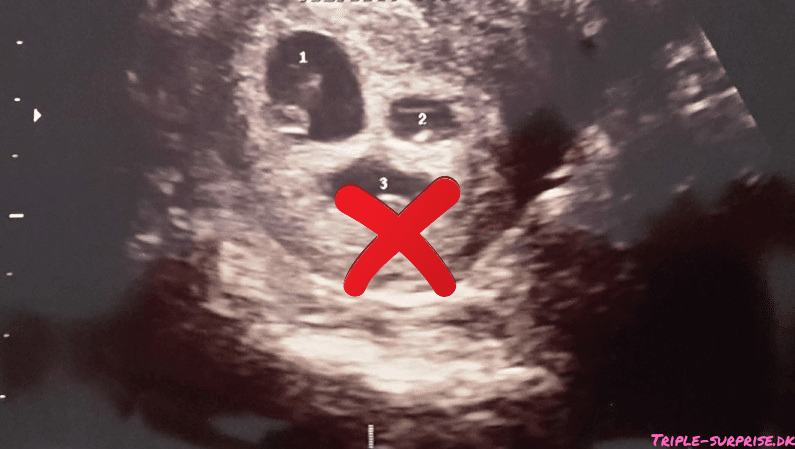

Jeg var alene på scanningsklinikken da jeg fik at vide jeg havde tre små liv i maven, og ikke bare ét. Jeg hørte tre små hjerter slå. Og samtidig skulle jeg forstå hvad jordemoderen sagde: “I vil nok blive rådet til at reducere” (altså hvad – aflive en??!)

Fakta er at en trillingegraviditet er “Høj-risiko” – altså høj risiko for at abortere og høj risiko for at føde meget for tidligt – eller ekstremt for tidligt. Vi fik et stykke papir udleveret på sygehuset med procenttallene for det ene og det andet, og så skulle vi gå hjem og tænke over det. Hele essensen er jo at ved at reducere til 2 fostre, så har de 2 bedre chancer.

På en måde var vi jo heldige at finde ud af at der var tre allerede da jeg var 7 uger henne – vi havde god tid.

Vores umiddelbare tanke var helt klart at “Det må vi jo gøre noget ved!” men en så stor beslutning kræver grundig overvejelse. Det her ville jo påvirke resten af vores liv. Min allerførste skræk var, om min krop kunne holde til en trillingegraviditet. Med tre kejsersnit i bagagen, for snævert bækken og en hofte med slidgigt var jeg ærlig talt rædselsslagne for at sætte mit helbred liv på spil og at det skulle gå ud over vores tre store børn.

Allerede ved første scanning på OUH blev jeg dog beroliget; tidligere kejsersnit var intet problem og de ville holde godt øje med mig, så jeg havde ikke noget at være bange for. Vi skulle dog være forberedt på at jeg skulle “sygemeldes” fra uge 20 og at jeg nok ville blive indlagt den sidste del af graviditeten til aflastning. “Okay- det klarer vi jo nok…”